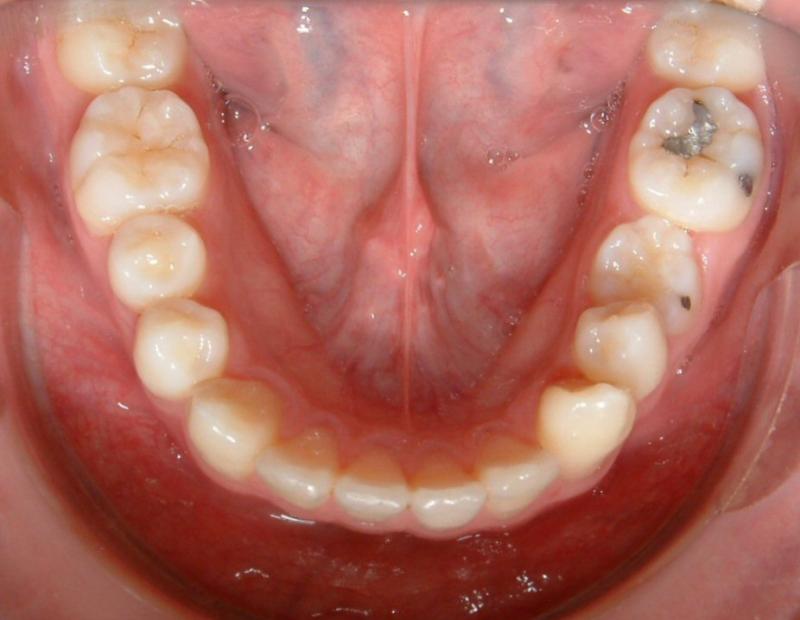

Figs. 1-7 are used with the intention of showing a case that requires a TAD. Not all orthodontic cases need TADs. The upper midline is coincident with the facial midline (not shown), but the lower midline is shifted to the patient's left about 4 mm. The lower left deciduous second molar (LLE) was ankylosed with hypo alveolar crest (radiograph not shown). The treatment plan was to extract LLE, then protract the lower left 1st molar (LL6) to close the gap of missing LLE, and to shift the lower midline to the patient's right (to match the upper midline). It would be impossible to achieve these treatment objectives with traditional technique (w/o a TAD).

Fig. 1. The lower midline is shifted to the patient's left.